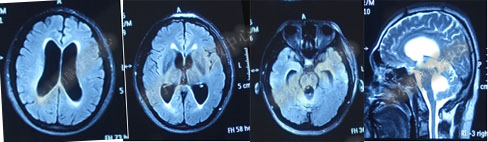

第4次出院后11天即2018年4月15日(分流术后284天,第2次的软性内镜术后179天),因引流管堵塞第5次住入该院,引流管内白色絮状物增多,引流管被堵塞。入院当天复查头部CT(图-10)显示脑室系统仍扩张。

图-10:2018年4月15日头部CT

第5次入院第2天即2018年4月17日,脑室腹壁外引流管堵塞,意识恶化,复查头部CT(图-11)示全脑室系统又较前扩大。当天急诊行左侧脑室穿刺外引流术。脑脊液化验外观黄色浑浊,并且送培养,结果是无菌生长。

图-11:2018年4月17日头部CT脑室扩张又加重